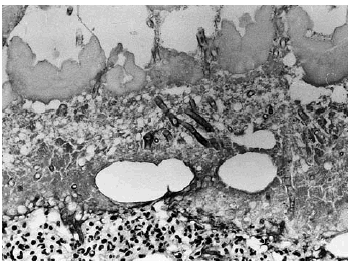

A los pocos días le apareció una lesión nodular dolorososa en el costado, de 6 cm de diámetro, de superficie eritematosa y crecimiento rápido. Se realizó biopsia cutánea, enviando muestra para cultivo y para estudio histopatológico. En el cultivo se identificó Aspergillus flavus y el examen histológico mostraba en piel una lesión centrada en el tejido celular subcutáneo (fig. 1) donde se observaba un área de necrosis amplia de los lobulillos adiposos (figs. 2 y 3), en cuyo interior se reconocían abundantes nidos de hifas fúngicas tabicadas, positivas con las tinciones de PAS y metenamina plata.

Fig. 3.--Detalle de la figura anterior en la que se reconocen claramente las hifas de Aspergillus distribuidas difusamente en el área de necrosis.